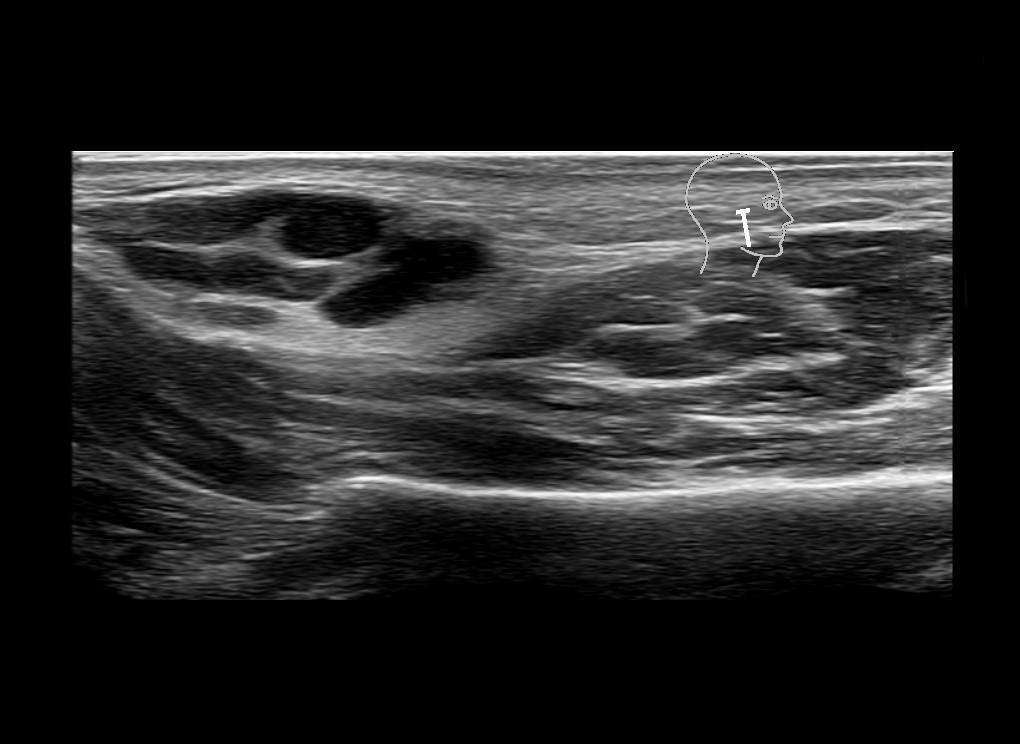

Filler injections in the parotid gland may go unnoticed, however, inflammatory reactions and abscesses may occur. Hypervascularity can be seen with color doppler. Filler deposits are supposed to be injected into the superficial fatty layer . The space to inject into this layer may be limited. Routinely we measure a width of 2-4 millimeters with sometimes subcutaneous layers being less than one millimeter thick.

Study the first image to recognize the different layers. If you are sure about the layers, swipe to the second image to view the answer (if applicable).